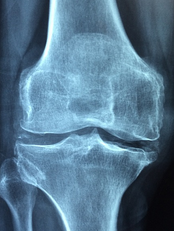

2. **관절염 증상 개선**: 관절염은 염증성 질환으로, 주요 증상은 관절의 통증, 뻣뻣함, 관절 기능 범위의 제한입니다. MSM은 이런 관절염 증상을 개선하기 위한 대체 요법으로 사용되곤 하는데, 이는 MSM의 강력한 소염작용 때문입니다. 일례로, 한 연구에서는 무릎 관절염이 있는 환자 49명을 대상으로 12주간 MSM을 섭취하게 했습니다. 그 결과 MSM을 섭취한 환자들의 무릎 통증과 경직이 감소하고 신체 기능이 개선되었습니다.